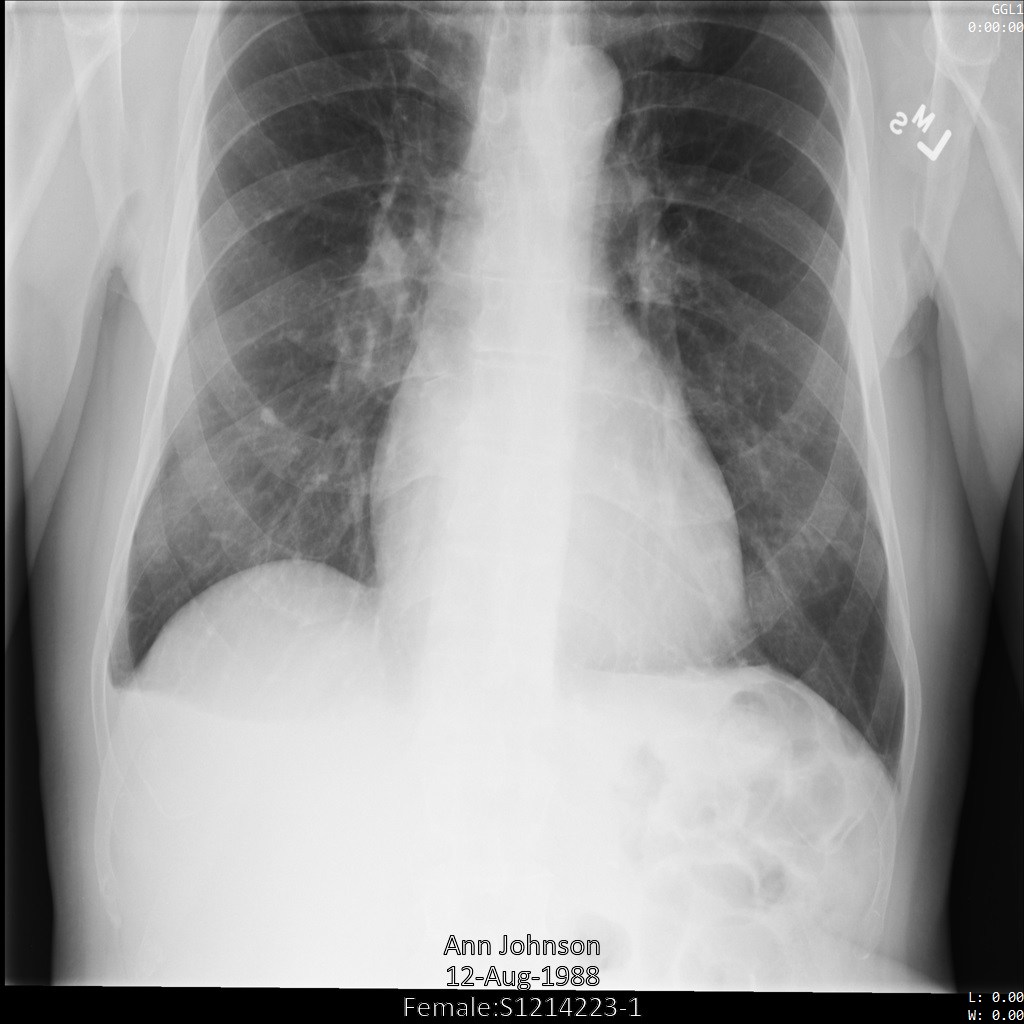

以下各部分提供的示例展示了如何使用各种方法对 DICOM 数据进行去标识化。每个示例都会提供去标识化后的图片输出。每个示例都使用以下原始图片作为其输入:

xray_original

您可以将每个去标识化操作的输出图片与该原始图片进行比较,以查看该操作的效果。